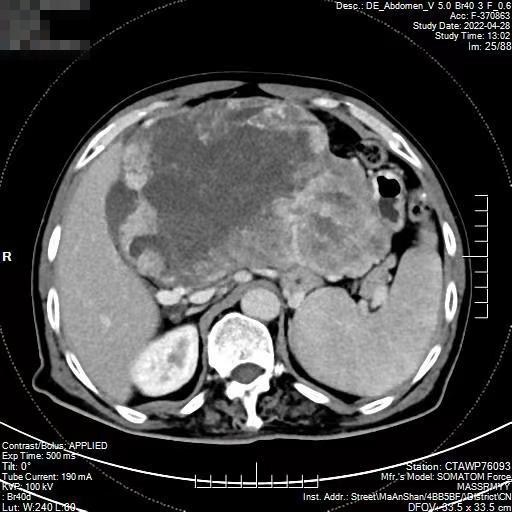

日前,一向身體健康的董先生感覺腹脹,主訴“肚子鼓起來了”。在家人的陪伴下,董先生來到市人民醫(yī)院東院(秀山醫(yī)院)普外綜合科診治。醫(yī)生查體發(fā)現(xiàn)董先生腹腔內(nèi)有腫塊,做CT檢查顯示一個(gè)約20cm腫塊位于肝胃間隙,血供豐富,推擠肝臟、壓迫胃壁。這樣的腫塊生長迅速,常常危及生命。

普外綜合科團(tuán)隊(duì)完善相關(guān)檢查后,為董先生制定詳盡的手術(shù)方案。術(shù)中驗(yàn)證了CT檢查所見的情況,腫塊上布滿了血管,幾乎占滿了整個(gè)上腹部,部分已侵犯胃壁及大網(wǎng)膜。情況十分危險(xiǎn),巨大的腫塊可隨時(shí)引起出血、腫瘤破裂、肝臟或腸道損傷等并發(fā)癥。手術(shù)團(tuán)隊(duì)小心謹(jǐn)慎地分離周圍組織,斷扎腫瘤血管,經(jīng)過“步步驚心”謹(jǐn)慎細(xì)致的剝離和嫻熟技巧,終于將腫瘤及部分胃壁大網(wǎng)膜完整切除。術(shù)后董先生恢復(fù)很快,他笑著說道:“現(xiàn)在吃東西很香,肚子大小正常了,你們可真是巧手??!”